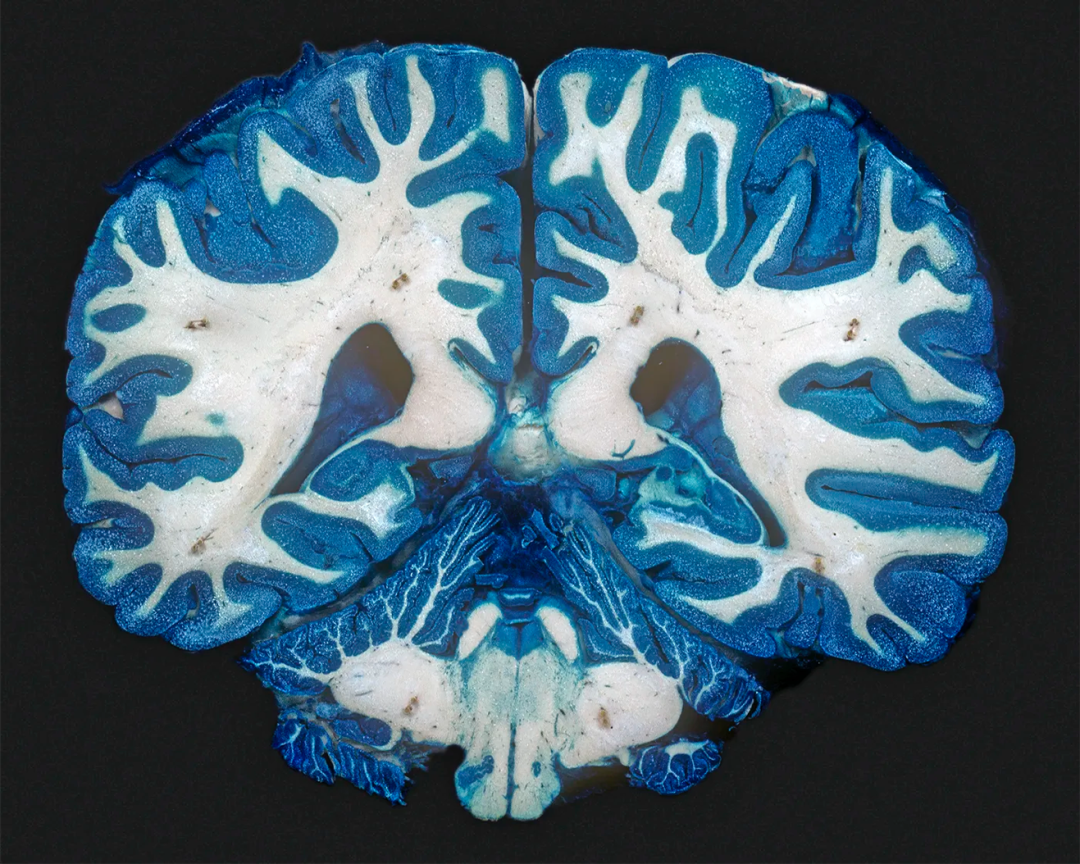

▷ 图注:研究表明,在慢性抑郁症患者的大脑中,富含神经纤维的“白质”区域的连接较少,而造成这种差异的原因未知。图片来源:Science